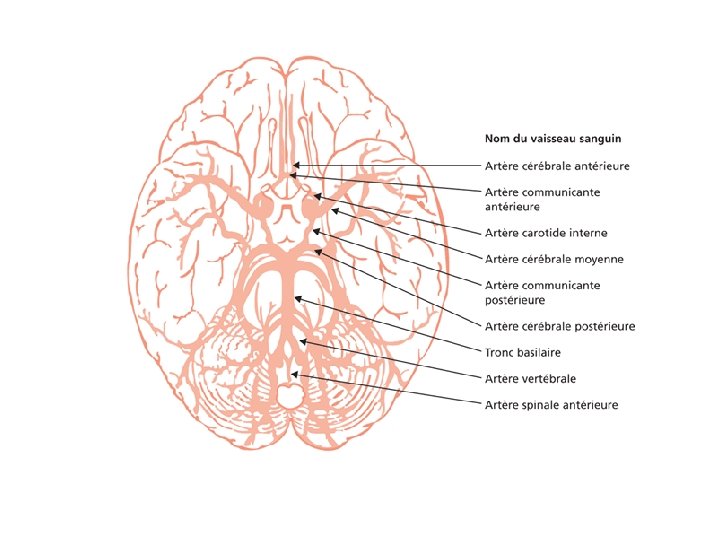

Anatomie • • • Scalp Os Méninges Cerveau Vaisseaux

Les différentes lésions 2/2 • Hématome extra-dural – L'hématome extra-dural ou épidural est une accumulation de sang entre l'os du crâne et la dure-mère (enveloppe fibreuse du cerveau faisant partie des méninges). L'hématome extra-dural est une urgence chirurgicale absolue. Il se développe en quelques heures et peut entraîner la mort du patient par engagement cérébral si rien n'est fait. • Hématome sous-dural – Il s'agit d'un épanchement sanguin situé entre, en dehors la dure-mère, et en dedans l’arachnoïde. Il peut survenir de façon aiguë, au cours des heures suivant le traumatisme (hématome sous-dural aigu). Il est alors fréquemment associé à une contusion cérébrale dont peut dépendre le pronostic. Il peut aussi se constituer à bas bruit, et se démasquer quinze jours, voire des semaines après un traumatisme relativement peu important (hématome sous-dural chronique). • Hémorragie intracérébrale – Il s'agit d'un saignement à l'intérieur du parenchyme cérébral. • Hémorragie méningée – Une hémorragie méningée est observée dans 1/3 des traumatismes crâniens sévères. Elle peut être secondaire à la lésion d'un vaisseau méningé, ou bien à une suffusion hémorragique à partir d’un foyer de contusion du cortex cérébral.